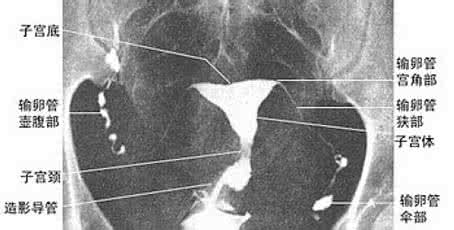

输卵管造影是一种很常见的检查方法,这样可以很好的将输卵管的情况表现出来,更利于观察,这时,医生可以根据实际情况,对于女性输卵管是否有堵塞、不通、粘连的现象进行判断。以下就是关于输卵管造影术要做多长时间详细介绍。